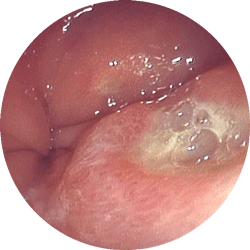

十二指腸潰瘍1

十二指腸潰瘍

お腹が張る,つかえる感じで

来院

内服薬にて1ヶ月で治癒